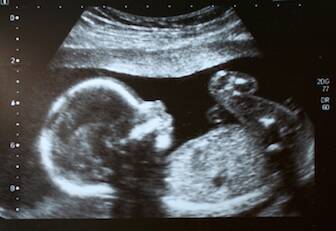

By the second pregnancy ultrasound at RMA Lehigh Valley (at 6.5 weeks), we can actually watch the fetal heart beating on the screen and even measure the fetal heart rate. We don’t listen to the heart beating since the use of Doppler exposes the baby to higher frequency sound.

The ultrasound machine can calculate the heart rate when we measure the distance between the motion of the heart beats. From seven weeks gestational age and for the remainder of the pregnancy, the baby’s heart rate usually measures between 120 and 180 beats per minute. Compare that to a normal resting adult heart rate of 60 to 100 beats per minute and it’s quite a difference.